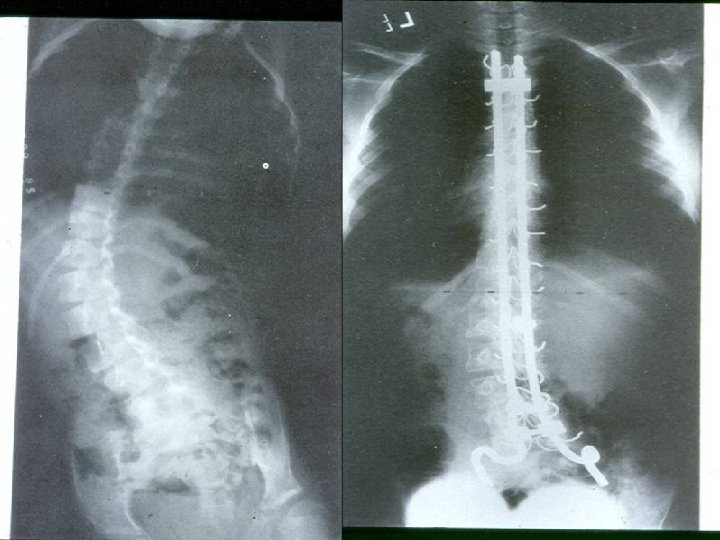

Deformities Lower limb : Ø Hip adduction/flexion/internal rotation Ø Knee flexion Ø Feet equinus / varus or valgus Ø Gait scissoring Spine : kyphoscoliosis

The two most important x-rays during follow up